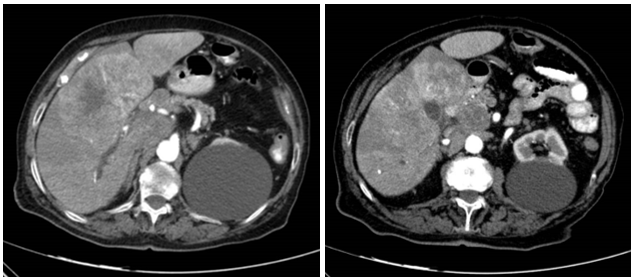

TAC abdominopélvico: lesión hepática de 10x7.5x8 cm en segmentos 4, 5 y 8 sugestiva de hepatocarcinoma, que condiciona ectasia distal de vía biliar intrahepática. Múltiples adenopatías en hilio hepático y espacio portocava con efecto masa sobre la cabeza pancreática, y paraaórticas anteriores e izquierdas supra e infrarrenales. Lesión mesentérica de 2x1.5 cm en bifurcación aortica compatible con lesión secundaria.